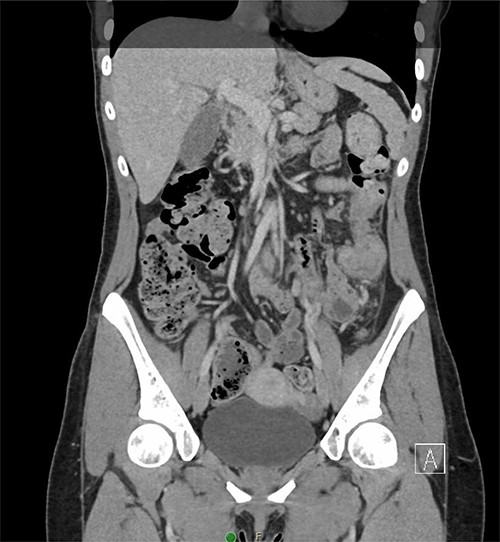

A 31-year-old woman initially presented to the ED with 2 days of left flank pain and a 1-year history of abdominal pain and bloating. The patient reported having had a fever (100.5 Tmax) and recurrent non-bloody loose stools. Vitals upon presentation to the ED were reassuring and the patient was afebrile. Initial physical exam was normal with the exception of costovertebral angle tenderness. Labs were significant for elevated c-reactive protein and leukocytosis. CT abdomen revealed segmental wall thickening of the descending colon with adjacent inflammation and associated with diverticular disease favoring acute diverticulitis (Figs 1 and 2). There was no evidence of nephrolithiasis. The patient was discharged on a 7-day course of Augmentin and was scheduled for colonoscopy.

Coronal CT demonstrating segmental wall thickening of the descending colon with adjacent inflammation favoring acute diverticulitis or segmental colitis.